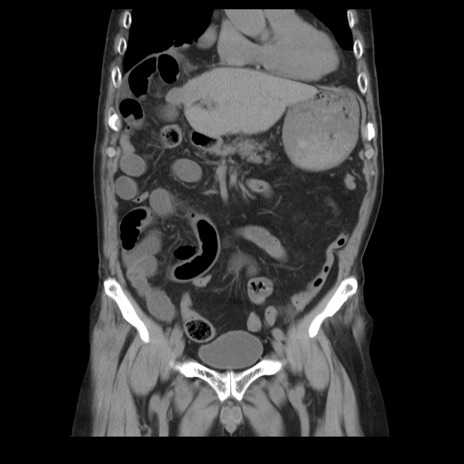

症例21(冠状断像)

【症例】70歳代男性

【主訴】腹痛

【現病歴】肝硬変・肝細胞癌にてかかりつけの方。約9時間前に食後より腹痛出現。症状が徐々に増悪し、嘔吐出現したため来院。

【既往歴】肝硬変、肝細胞癌(RFA、TACE後)

【身体所見】意識清明、表情苦悶様、BT 36℃、BP 129/78mmHg、P 88bpm、SpO2 97%(RA)、右上腹部から心窩部にかけて圧痛あり、反跳痛なし、筋性防御あり。

【データ】WBC 5800、CRP 0.16